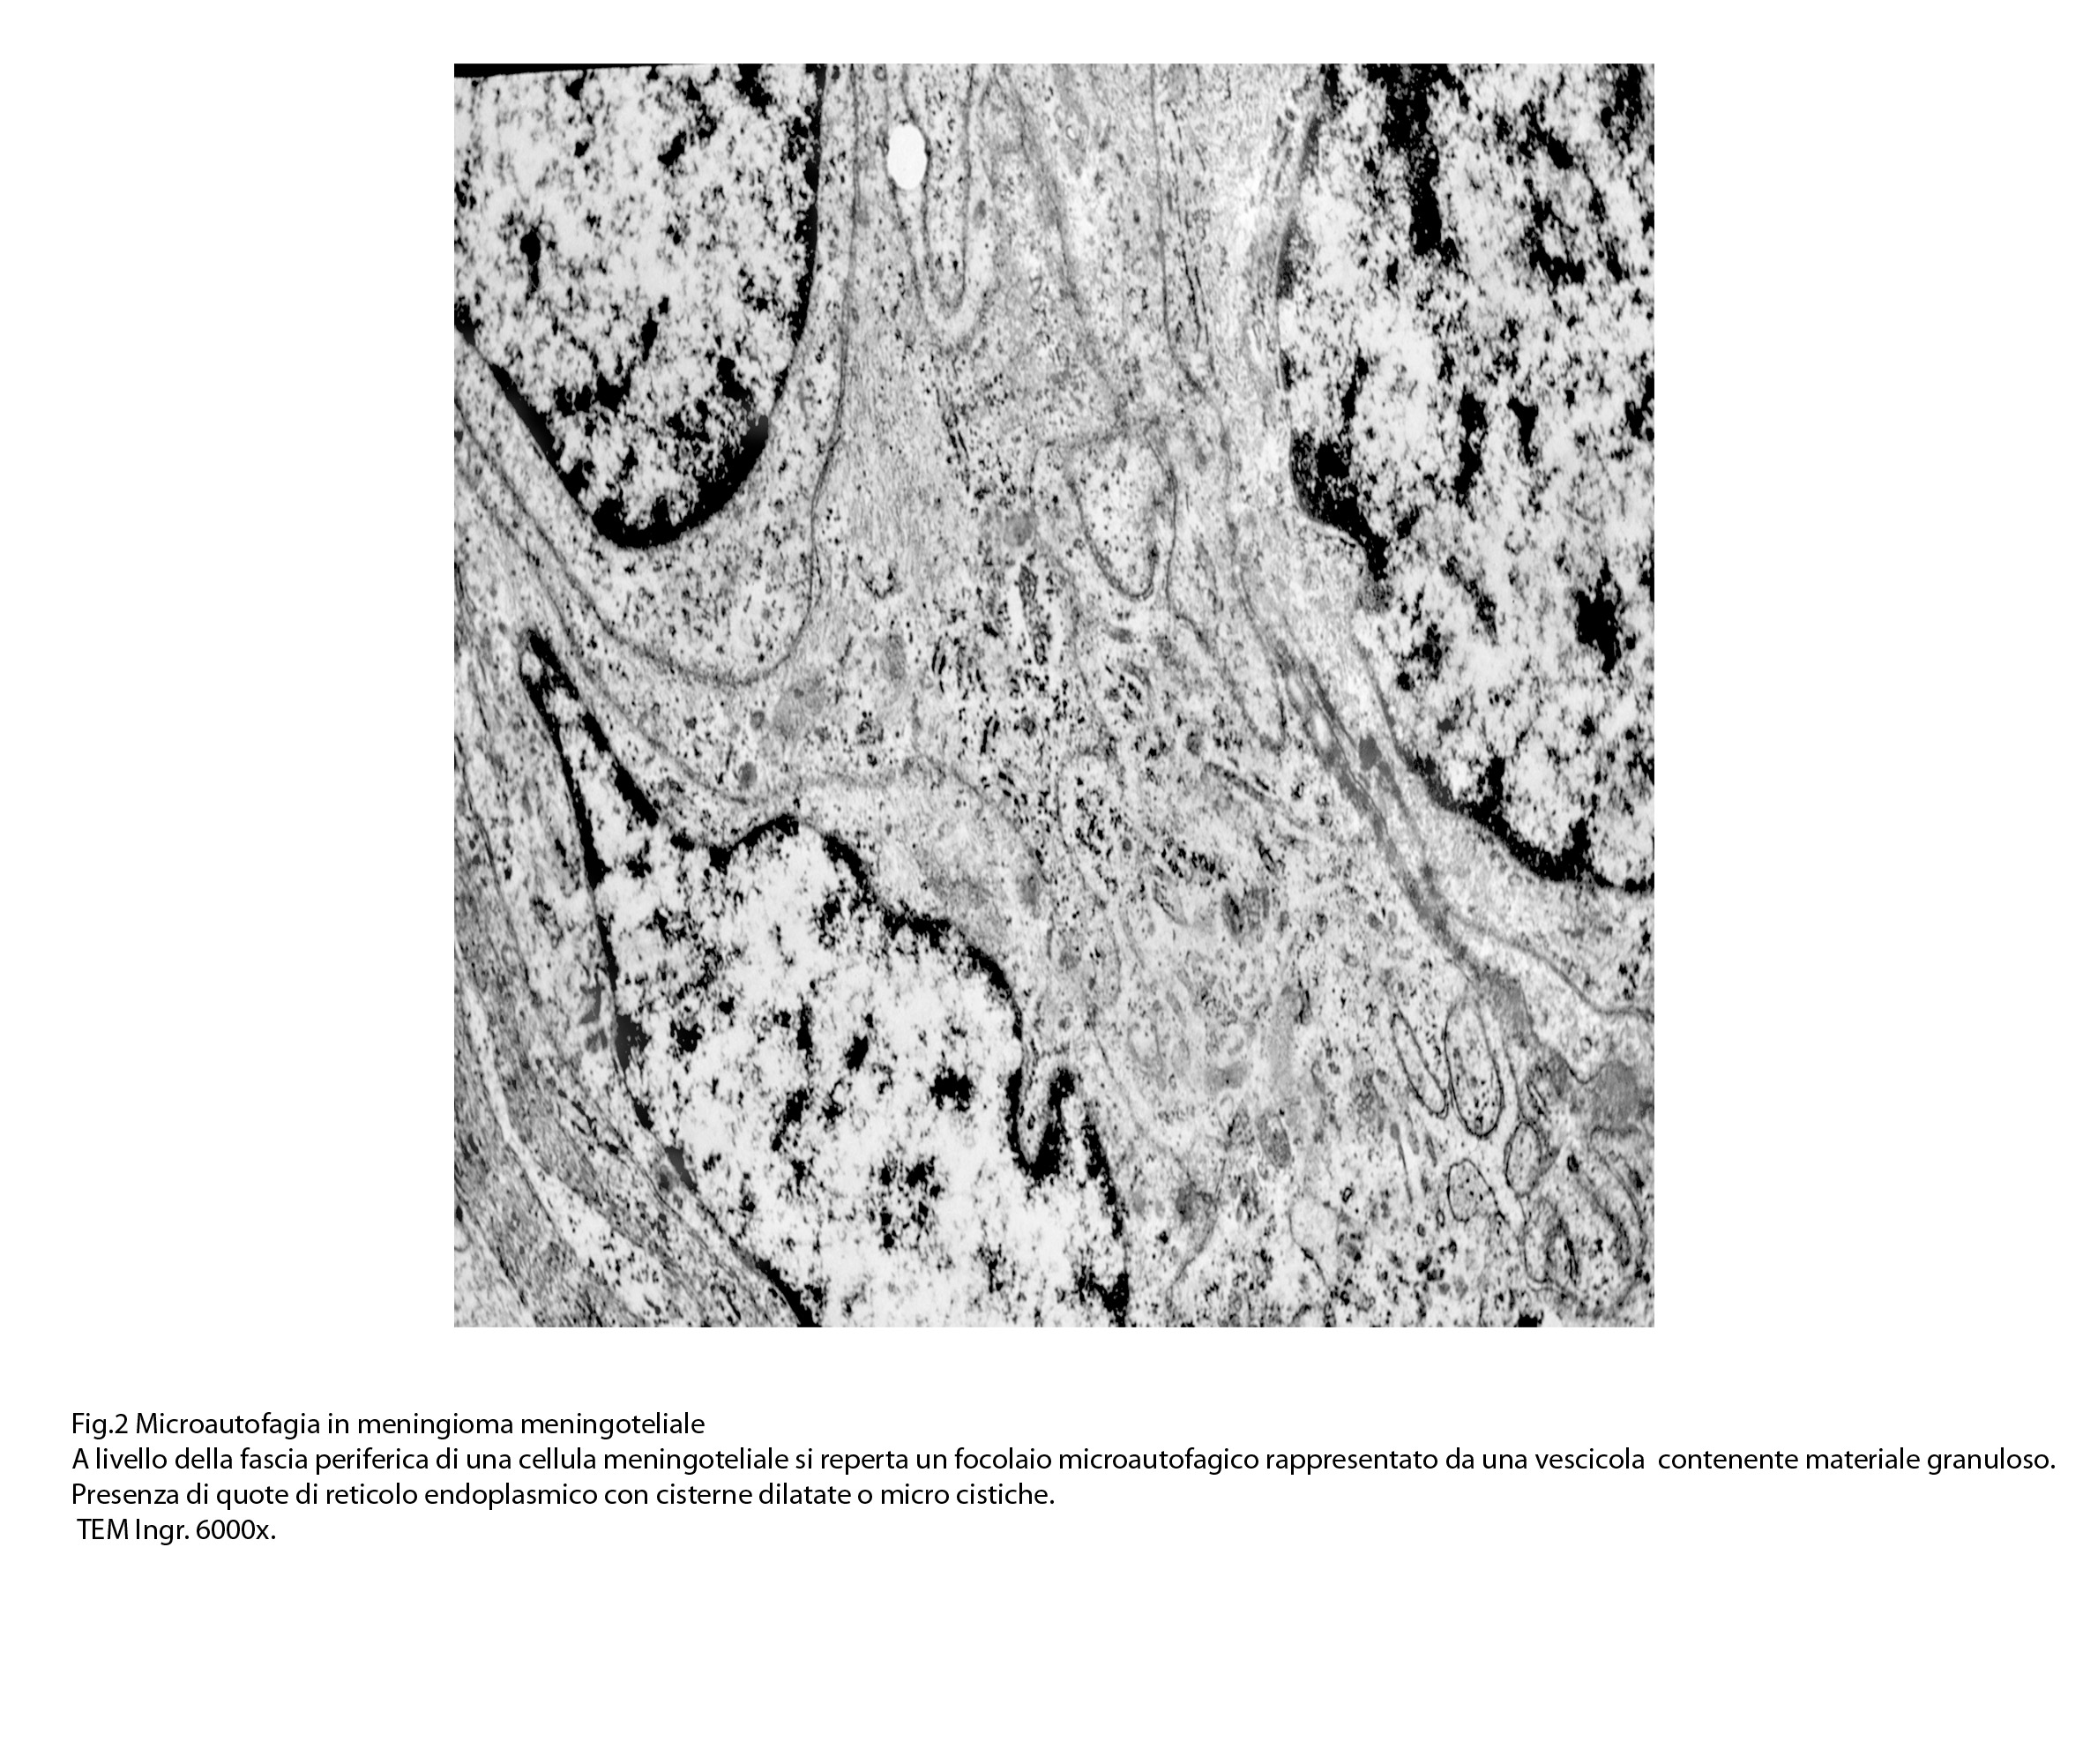

1) MICROAUTOFAGIA

Nel citosol si repertano vescicole di piccole dimensioni delimitate da una membrana di contorno a mono strato. Il loro lume è occupato da materiale amorfo e da corti filamenti distribuiti in modo disordinato.

Queste vescicole sono distribuite in modo irregolare, anzi casuale e si ritrovano ad essere isolate o riunite in piccoli aggregati formando un’immagine definita corpi multivescicolari.

Frequentemente questi focolai si ritrovano commisti ad altri aventi i caratteri della macroautofagia e sono in parte da questi mascherati. A parte questi particolari reperti,il citosol è occupato da numerosi mitocondri di piccole dimensioni e di forma rotondeggiante e di aspetto compatto,da ergastoplasma rugoso e da quote ben rappresentate di reticolo endoplasmico e di strutture lisosomiali.

Alcune cellule meningoteliali sono sedi, sopratutto a livello delle fasce periferiche, di ampie vescicole, di forma irregolare le quali sono demarcate da una membrana a mono-strato; gli spazi di queste vescicole sono in buona parte occupati da materiale amorfo, da frammenti filamentosi e da organuli intracitoplasmatici,tutto sottoposto a degradazione.